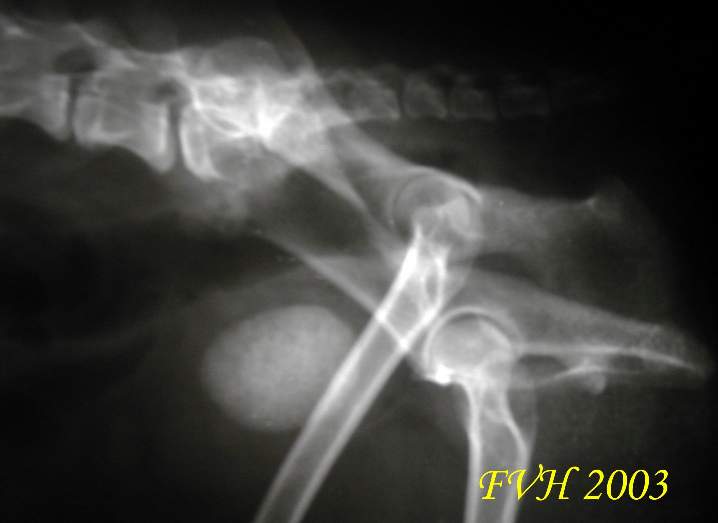

放射線檢查發現的膀胱結石

(urinary bladder uroliath)